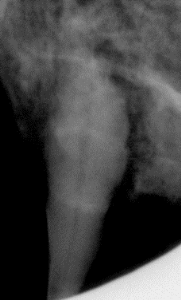

A true story from our hospital: Brayden is a 14-year-old domestic short-hair cat. His owner noticed that sometimes he would paw at his mouth, so he suspected that there was something wrong with Brayden’s teeth. Brayden being a well behaved lil guy let the veterinarian do a rather good visual check of his teeth. Aside from a small amount of tartar on a couple of teeth, there were no signs of a deeper infection or disease. Brayden’s owner opted to go ahead with a dental procedure including radiographs, just to reverse the infection that was present (plaque and tartar). All involved were expecting a routine procedure. When the radiographs were complete they revealed that ALL four canines and 2 molars were affected by resorptive lesions at the roots. This means the roots were disintegrating and resorbing into the jaw below the gum line and this can be quite painful. The affected teeth were removed and Brayden is much happier now that he is pain-free. He still much enjoys his kibble.

If radiographs had not been done Brayden would still be dealing with the painful dental disease and they likely would have fractured once there was no longer enough root to anchor them.

Below is one of Brady’s radiographs and him happily snoozing at home afterwards.